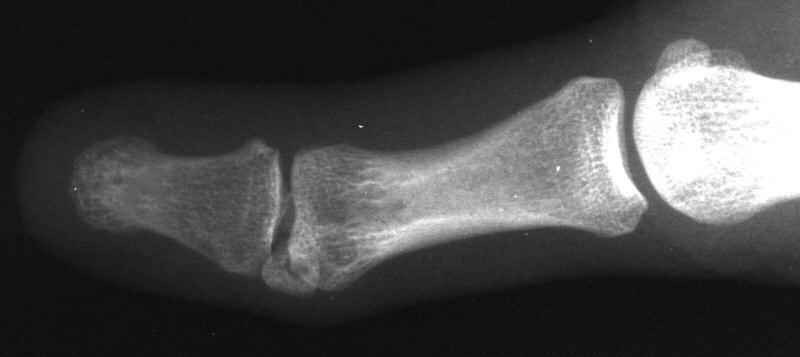

Case 3. 21 year old woman with pain developing in a congenitally angulated thumb.

Radiographs show a juxtaarticular ossification with  subchondral cyst formation of the bone interface with the lateral phalangeal head and lateral angulation of the proximal phalanx articular surface.

This was treated with excision of the mass and corrective closing wedge osteotomy of the proximal phalanx.

There was no articular cartilage on the pseudojoint, with  arthritic type reactive changes.